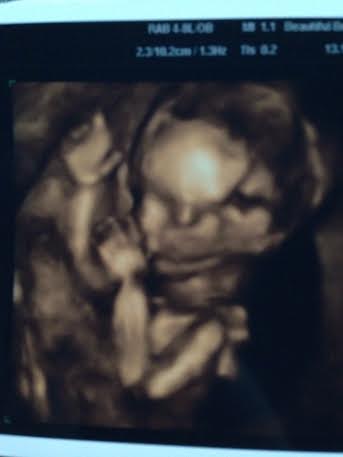

I am loving all the bumps and boobs Here is a pic of me at 20 weeks the other day wearing the sweater dress I had a meltdown about because I felt gross in it. I had my A/S today and everything looked perfect. Our little guy was not very cooperative though so I couldn't get a 3D pic. My sister is an ultrasound tech so she will take me in and scan me another time to get some good face pics. Here is his profile with a knee by his mouth and a good one of his feet. He was curled up with his arms and legs covering his face when they tried to do 3D. Little stinker!

I had my A/S today and everything looked perfect. Our little guy was not very cooperative though so I couldn't get a 3D pic. My sister is an ultrasound tech so she will take me in and scan me another time to get some good face pics. Here is his profile with a knee by his mouth and a good one of his feet. He was curled up with his arms and legs covering his face when they tried to do 3D. Little stinker!